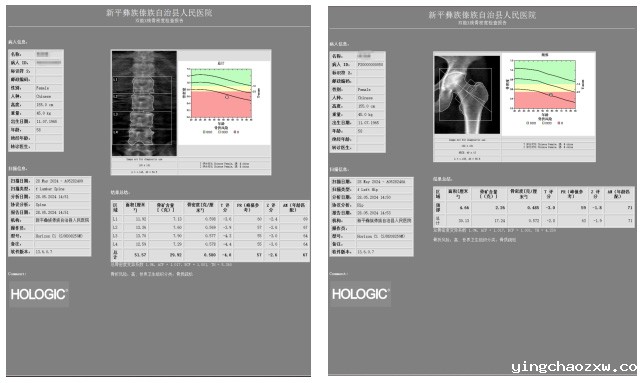

骨质疏松被称为“隐形杀手”,平日不易察觉,可一旦出现腰酸背痛身高变矮,驼背时就难以挽回。为了让县域各族群众在家门口就能精准进行骨密度测量,及时预防和治疗骨质疏松,新利官网登录于近期引进Horizon-Ci双能X线骨密度仪,并正式投入临床使用,诚挚欢迎广大患者朋友前来咨询就诊!

Horizon-Ci双能X线骨密度仪是全球最先进的骨质疏松检测设备,集快速精确数字成像技术和精美的人体工程学设计为一体,能进行骨密度测量、全面骨骼健康评估及高级体脂成分分析,有效满足了骨质疏松、肥胖及心血管疾病诊断的需要。由于其辐射剂量极低、扫描精准度高和诊断报告指标全面,是国际公认的骨质疏松诊断的“金标准”。